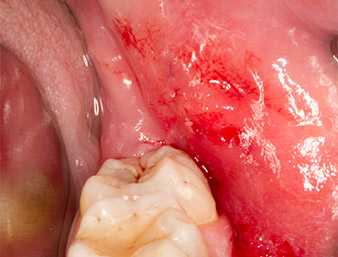

Dopo l'anestesia tronculare e l'anestesia locale, il sito operatorio è stato aperto e il tessuto molle esposto per l'accesso retromolare boccale (Fig. 3).

incisione sulculare

Fig. 3: L'incisione sulculare ha inizio a metà del dente 36 (LL6), con estensione distale sul ramo ascendente.

Il tessuto al di sopra del residuo di radice non era completamente ossificato ed era costituito per la maggior parte da tessuto di granulazione modificato dall'infiammazione (Fig. 4).